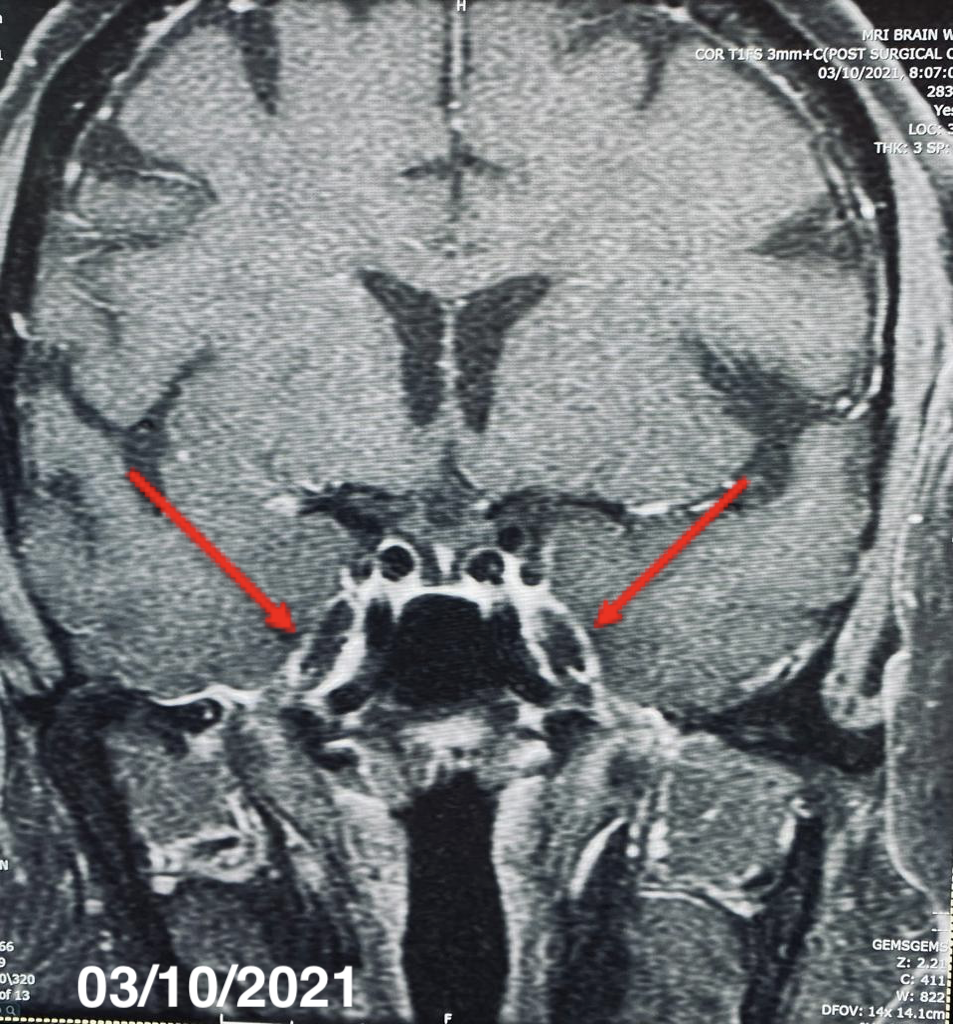

A pituitary magnetic resonance imaging (MRI) study with and without contrast revealed the presence of infiltration of the pituitary gland (Figure 1), stalk and bilateral cavernous sinus (Figure 2), and tentorium. A computed tomography scan of the thorax with contrast showed the presence of shotty mediastinal and hilar nodes with one large subcarinal node measuring 2 cm.

Figure 1. MRI resolution of the sellar and suprasellar mass with an empty, expanded sella in 2021.

Figure 2. MRI showing regional dural thickening and enhancement along the cavernous sinuses bilaterally extending into the optic chiasms and superior orbital fissures, complete resolution in images of 2021.

Patient Outcome. In 2022, 11 years after the diagnosis was made, the patient underwent a repeat MRI of the enhancing sellar and suprasellar mass, results of which showed ultimately an empty, expanded sella turcica. The patient has been clinically stable despite these changes. She is currently on a regimen of replacement of levothyroxine, 50 µg and prednisone, 7.5 mg daily. The patient remains symptom-free with complete recovery and remains clinically and biochemically euthyroid.